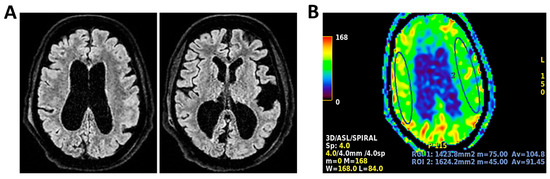

Background: Meningoencephalitis is a complex inflammatory condition of the CNS that can result in significant morbidity and mortality in critically ill adults. Accurate and timely neuromonitoring is essential for guiding management and improving outcomes. This study aimed to descriptively evaluate the prognostic value of early TCCD monitoring, particularly the pulsatility index, and its integration with conventional and perfusion MRI in patients with meningoencephalitis. Methods: We present an observational, retrospective, cohort study involving ten adult patients (median age 56 years, IQR 45.5–68.5; mean 55.9, range 35–76) with neurological syndromes caused by suspected or confirmed infectious meningoencephalitis. Etiologies included bacterial meningitis/meningoencephalitis (50%), viral meningoencephalitis (10%), neurotoxoplasmosis (10%), progressive multifocal leukoencephalopathy (10%), and undetermined origin (20%). Patients underwent TCCD and MRI within 24 h. In five cases, standard MRI sequences were acquired, while in the remaining five, perfusion imaging was performed using Arterial Spin Labelling (ASL). A favorable outcome was defined as survival with neurological recovery (Glasgow Outcome Scale > 5) at ICU discharge. Results: TCCD-derived PI provided valuable information on cerebral hemodynamics. PI values ≤ 1.25 were associated with favorable clinical outcomes and symmetrical MRI findings. Conversely, PI > 1.25 correlated with poor prognosis and often preceded MRI-detectable structural damage. When combined with ASL, PI mirrored the detected perfusion asymmetries and was associated with poor prognosis in fatal cases. Conclusions: Bedside TCCD can offer real-time assessment of cerebrovascular dynamics and, when integrated with conventional and ASL MRI, could enhance the understanding of pathophysiological processes in meningoencephalitis, supporting timely and informed decisions in neurocritical care.